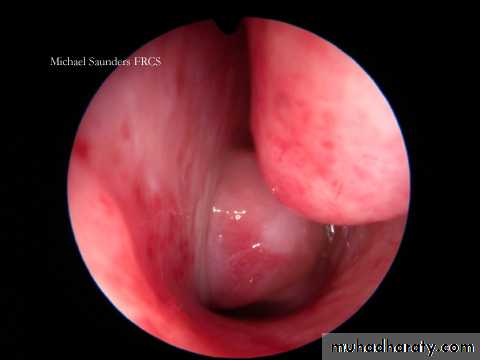

• Endoscopy: fissuring, hyperkeratosis followed by fibrosis, web formation in the postcricoid region.

1. Endoscopy and posterior rhinoscopy: smooth, rubbery lobulated mass in the nasopharynx.2. Middle ear effusion.